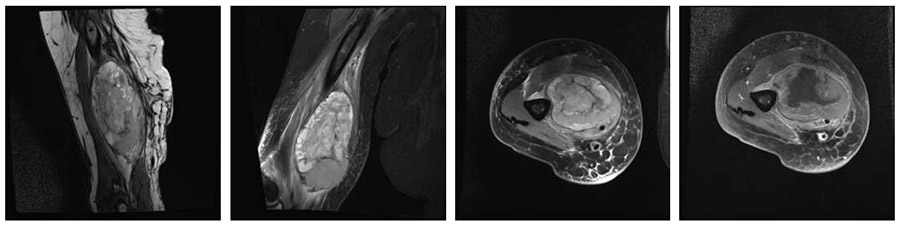

Ameliyat Öncesi: MR’da kol medialde humerus üzerine oturmuş nörovasküler yapıları itmiş düzensiz sınırlı heterojen kitle görülmekte